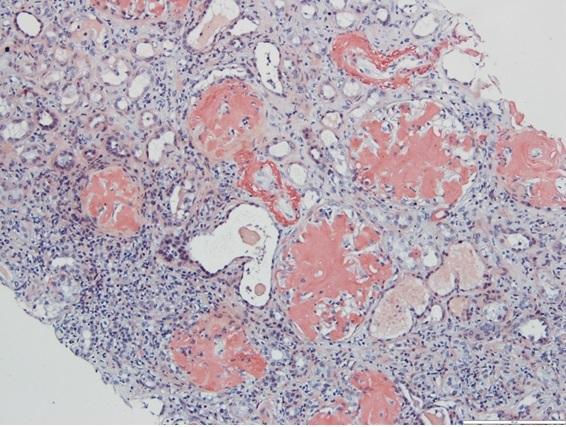

The systemic amyloidosis therapeutic market is witnessing notable advancements, driven by innovative treatments targeting complex protein misfolding disorders. Industry players are focusing on developing novel therapies that address different amyloidosis subtypes, which is accelerating business growth and transforming treatment paradigms. The evolving market dynamics, underpinned by...